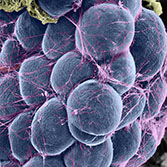

Histology is the study of the microanatomy of cells, tissues, and organs as seen through a microscope. It examines the correlation between structure and function.

Histology Guide teaches the visual art of recognizing the structure of cells and tissues and understanding how this is determined by their function. Rather than reproducing information found in a histology textbook, a user is shown how to apply this knowledge to interpret cells and tissues as viewed through a microscope.